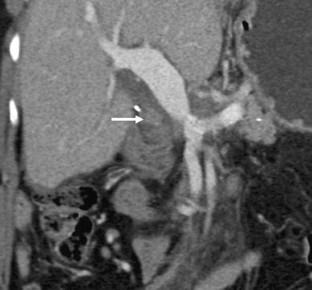

Fig. 5

Fig. 6